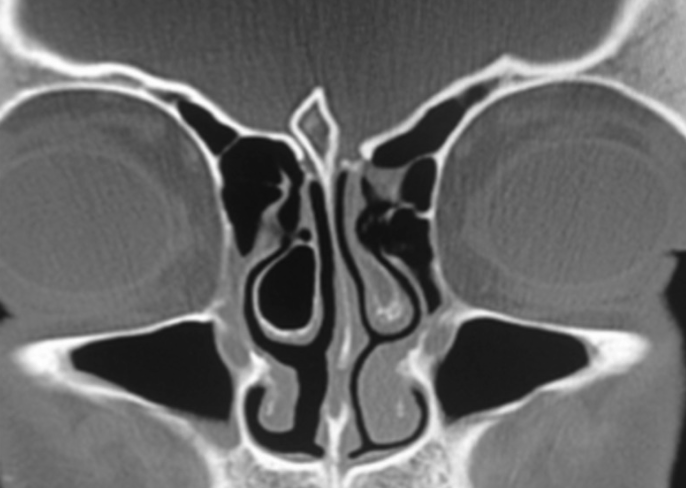

A 26-year-old male presents for a follow-up visit due to right-sided nasal discharge, obstruction, headache, and facial pain and pressure for the past 2 years, unresponsive to nasal saline, corticosteroids, antibiotics, and allergy medications. Upon review of charts, the patient is a nonsmoker and otherwise healthy without any comorbidities, including diabetes, asthma, GERD, and autoimmune diseases. His CT scan is shown below. Which of the following abnormalities is most likely causing this patient's symptoms?

D. Concha bullosa

D (Concha Bullosa)